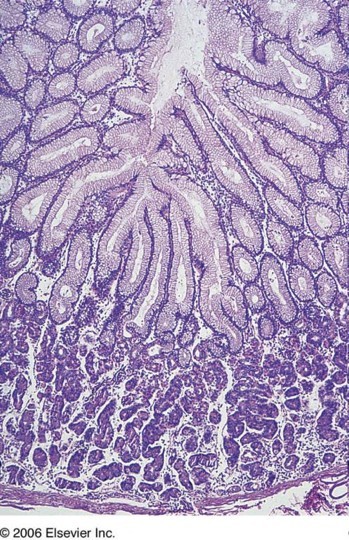

35 year old male presents with colicky abdominal pain and diarrhea 4-5 times a day for the past 2 years. What is his differential and diagnosis based on the colonoscopy image below?

Celiac sprue:

- Antibodies to gliadin

- Distal duodenum, proximal jejunem

- Loss of villi on histology

Colonoscopy= celiac sprue; see small-bowel scalloping